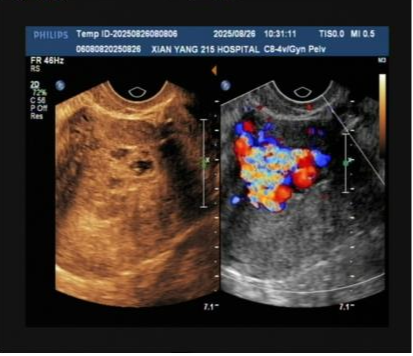

术前检查影像

检查结果很快传来,B超结果显示宫腔内残留组织伴丰富血流,高度怀疑“子宫动静脉瘘”;随后的MRI检查进一步证实,患者宫腔内不仅有异常病灶,邻近子宫前壁还出现多发流空信号——这意味着子宫动脉与静脉之间形成了异常通道,动脉血直接涌入静脉,一旦通道破裂,就可能引发难以控制的致命性大出血。